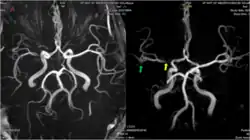

Middle cerebral artery angiography, showing stenosis

During an ischaemic stroke, blood flow through a cerebral artery is compromised. This frequently causes substantial injury to the area of the brain supplied by the artery, but not all of this territory is necessarily affected. A post mortem study of middle cerebral artery strokes demonstrated that the area of brain injury was often smaller than the total area supplied by the middle cerebral artery. Leptomeningeal collateral vessels from the anterior cerebral artery and posterior cerebral artery appeared to allow for perfusion of some brain tissue to persist, partially compensating for the loss of the major vessel.[6] This compensatory effect is however usually inadequate to maintain a normal blood supply.[11]